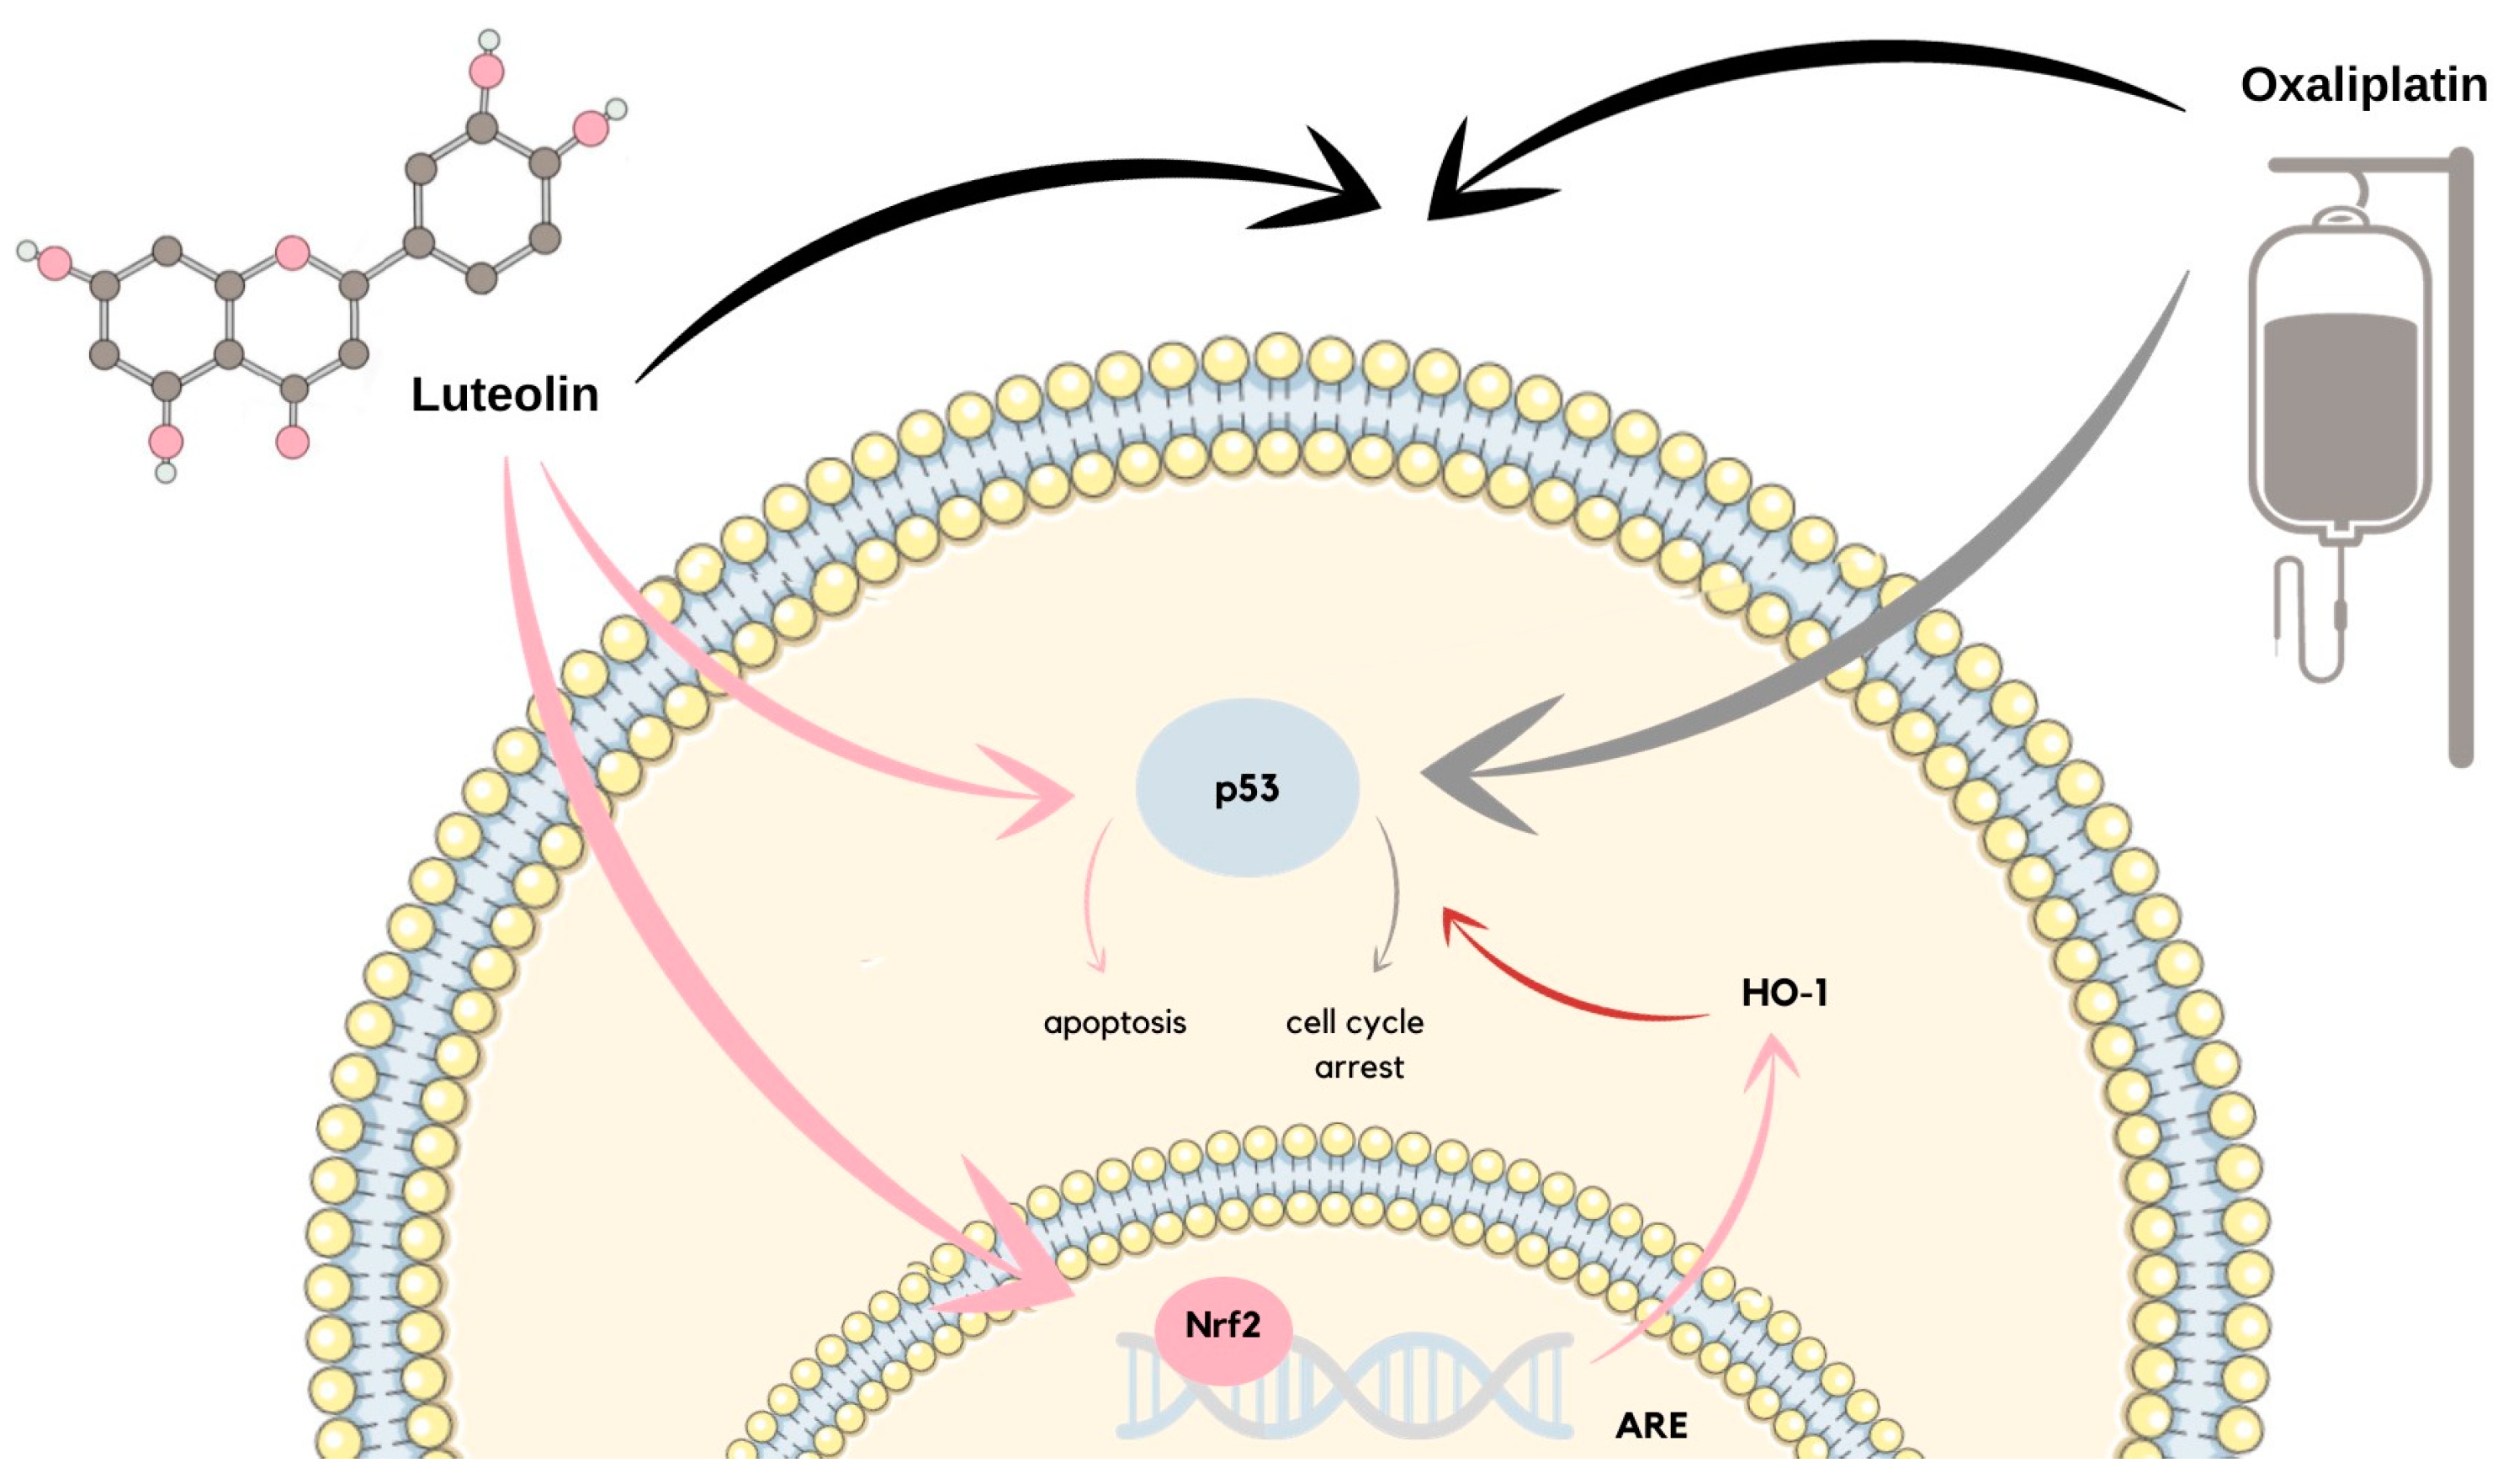

10. Colon Cancer